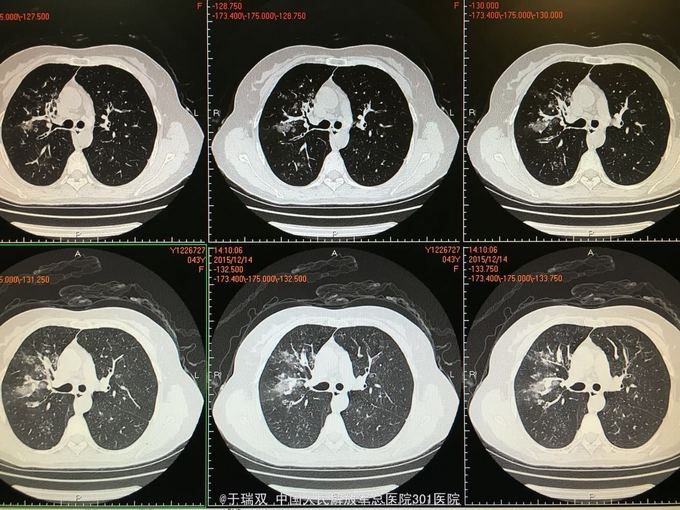

患者中年女女性,2014年10月无明显诱因出现咳嗽咳黄白痰,伴有喘息,自行药物治疗无好转。2014年11月下旬就诊于北京某医院诊断为“变应性支气管肺曲霉病、真菌性肺炎”先后给予伊曲康唑静滴及口服伏立康唑抗真菌、平喘等治疗后症状好转。复查CT炎症也吸收好转,于2015年3月停用以上药物。2015年11月患者再次出现上述症状,胸部CT见右肺班片状实变影,就诊于我院给予左氧氟沙星、西替利秦及化痰止咳治疗后略有好转,遂住院。2015年11月5日CT(图1、2),2015年12月14CT(图3、4、5、6)